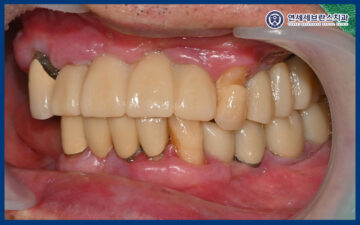

25.10.23

이렇게 치료를 마무리한 후,

약 3개월 뒤 환자분께서 내원하시어

정기 검진을 진행하였습니다.

검진 결과 임플란트와 주변 잇몸 상태

모두 특별한 이상 없이

안정적으로 유지되고 있었으며,

일상생활에서도 불편함 없이

잘 사용하고 계신 것을

확인할 수 있었습니다.

또한 안내해 드린 임플란트 관리 방법도

꾸준히 잘 실천해 주고 계셔서,

임플란트 주위 잇몸 역시

건강한 상태를 유지하고 있었습니다.

환자분께서는 오른쪽으로 씹는 걸 포기하고 살았는데

임플란트 이후 마음대로 먹을 수 있게 되어

너무 만족하게 되셨다고 하셨습니다.